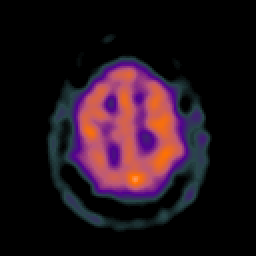

Glioma overlay -- Slice #23

[Home][Help][Clinical] Slice 23